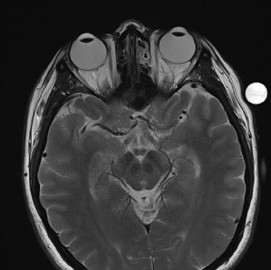

MRI scans have proven crucial in this research, he said. “The great thing about MRI is that it can non-invasively measure water content in the human tissue – the free water and water that is bound to proteins. This allows us to do longitudinal studies on how water content changes in the same individual in response to a potential therapy.”

A T2-weighted brain MRI scan showing a slice through

the eyes